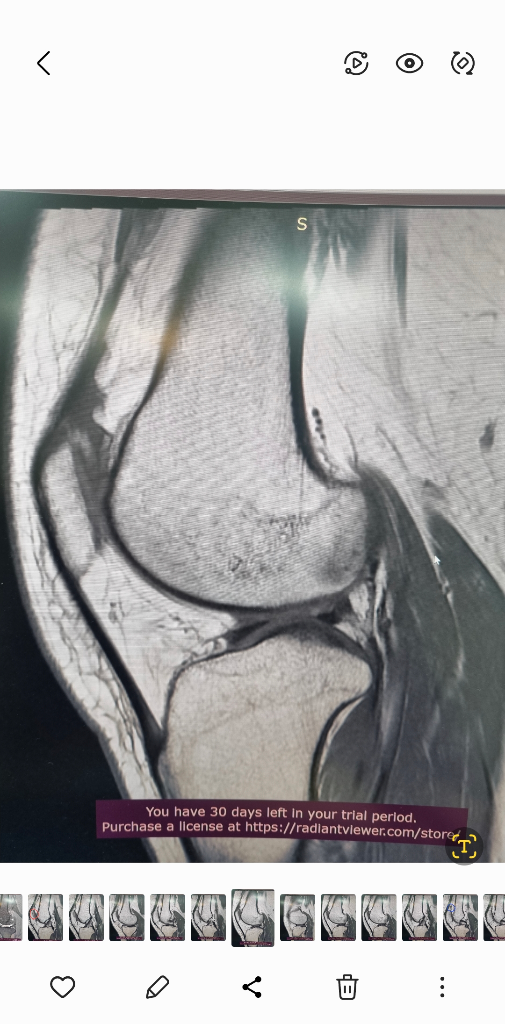

MRI는 신호가 다른 다른 사진들이 있을겁니다.

그런걸 종합적으로 판단해야 정확히 알수 있습니다.

검사한 병원에 판독요청하세요.